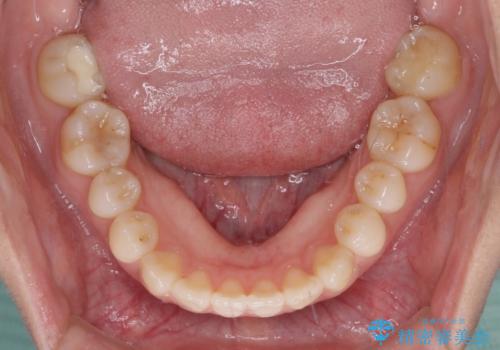

前歯のクロスバイトを治したい ワイヤー装置による矯正治療

- 前歯の反対咬合を気にして来院された患者様です。

マウスピース矯正も提案しましたが、しっかりと使用する自信がないとのことで、ワイヤー装置により矯正治療を行うこととしました。

クロスバイト改善まではスムーズに進みましたが、その後は強い舌の突出癖によりオープンバイトの期間が長く続きました。

舌のトレーニングをしっかりと実施してもらい、何とか仕上げることができました。